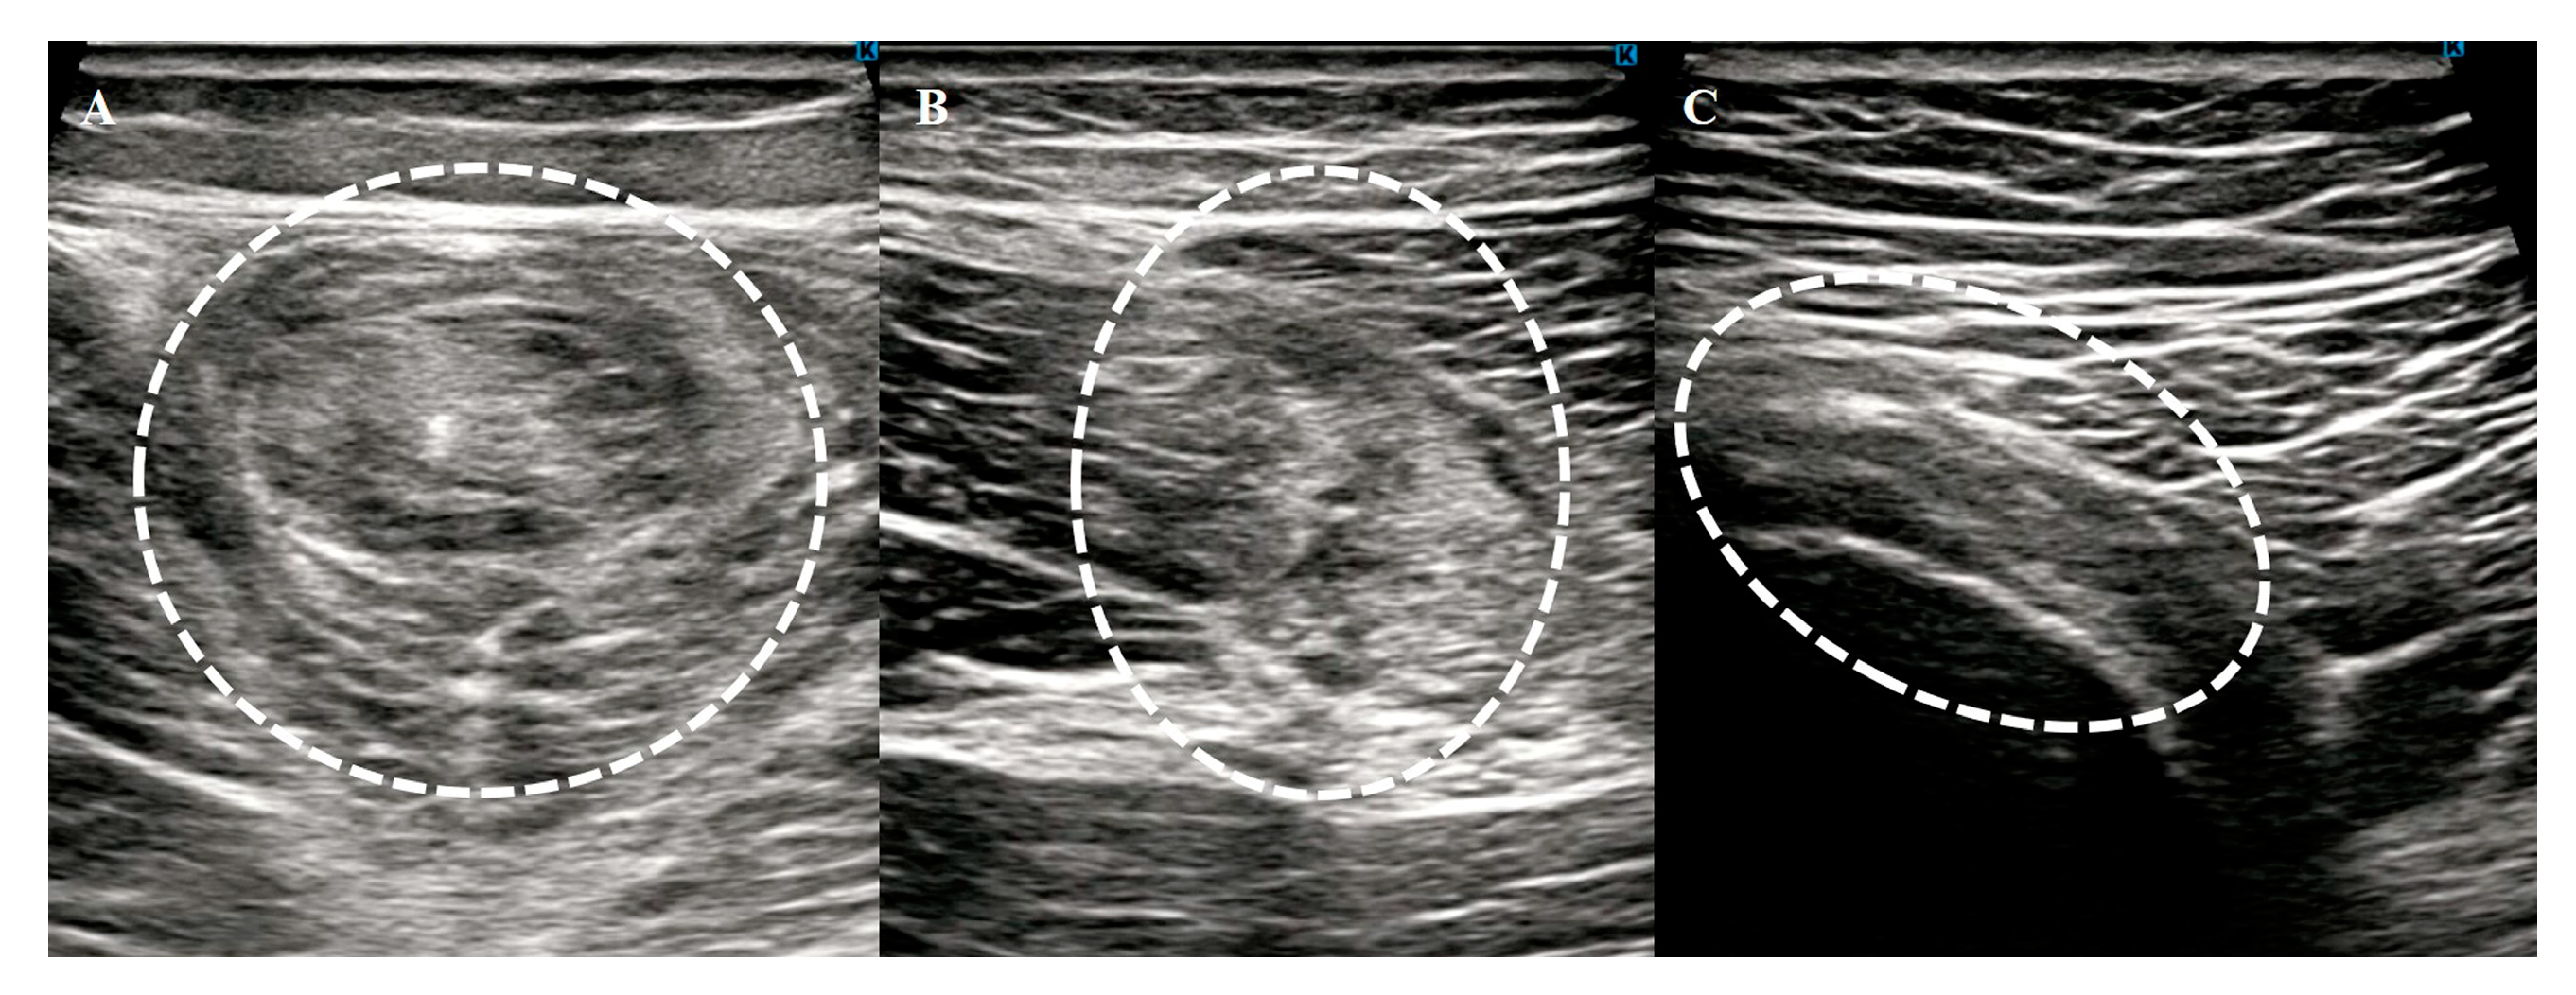

The patients were positioned supine with their hips and knees fully extended, allowing comprehensive scanning of the hamstring muscles from the ischial tuberosity to the knee joint in both the longitudinal and transverse planes. To ensure diagnostic accuracy, ultrasonography was performed on both the injured and uninjured sides for comparison. An abnormality was diagnosed if one or more of the following findings were observed (Figure 1):

• Changes in echogenicity or fiber disruption within the muscle.

• Edema or hemorrhage, identified as areas of increased echogenicity with or without visible fiber disruption in orthogonal planes.

• Hypoechoic fluid tracking along the fascial layer surrounding the muscle, indicative of intermuscular hematoma.

Figure 4. Typical ultrasonography findings in acute hamstring strain. Muscle (A), musculotendinous junction (B), and tendon (C) injuries. The white dotted circles indicates the injured area.